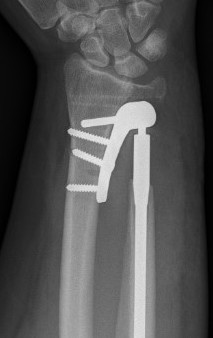

Suav-Kapanji

Technique

- distal radio-ulna arthrodesis with distal ulna pseuodoarthrosis

- distal ulna fused to distal radius with 2 screws

- distal ulna stabilised with half FCU

- interposition with pronator quadratus